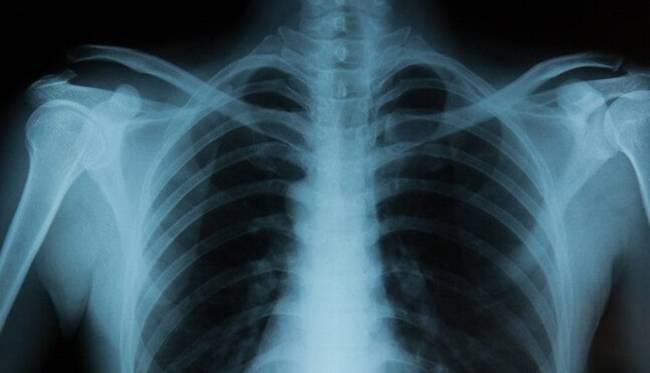

تشخیص هویت نژادی از روی تصاویر اشعه ایکس با هوش مصنوعی

تیم بینالمللی متشکل از محققان سلامت از ایالات متحده، کانادا و تایوان با در اختیار [...]